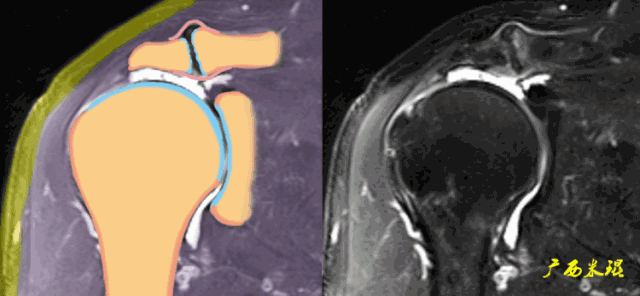

正常肩袖的MRI表现

各个序列肩袖均表现为均匀的低信号,是肌腱的延续。

(1)斜冠状位:平行于冈上肌腱长轴,主要评估冈上肌。